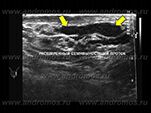

Обструктивное бесплодие диагностируют при сочетании отсутствия сперматозоидов в семенной жидкости с нормальным уровнем половых гормонов в крови. В ряде случаев имеет место увеличение придатков яичек и уменьшение объема спермы. Благодаря современным сонографическим системам экспертного класса при ультразвуковом исследовании в большинстве случаев можно увидеть уровень закупорки семенных путей мужчины. Таким образом, при правильно проведенном обследовании возможно запланировать наиболее подходящее для конкретного пациента лечение.